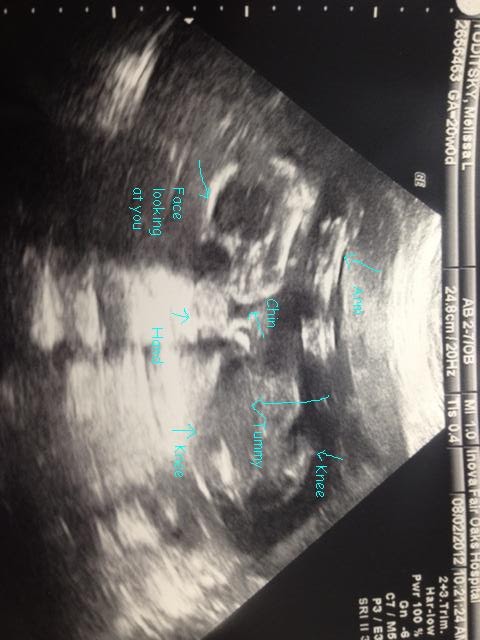

1) 24 weeks today....pictures to come tomorrow :)

5) Lots of movement from William the past week. If you know me, you know that I have been a little bit worried this pregnancy and with my anterior placenta, I wasn't feeling him move that often so I broke down and rented a doppler. (Honestly, I cannot believe I made it this far without getting one!!) It is amazing to hear William moving around and hear his heart beating nice and fast!!! The best part is that I feel him move, without the doppler, several times a day.

21 Weeks

Total weight gain/loss: At my doctor’s appointment today I was up 7 total.

Best moment this week: Really feeling him move all around and kicking!

Movement: Found out at my Level 2 that I have an anterior placenta which was why I wasn't really feeling him move (phew) but this past week he moves, kicks and rolls several times a day. He moves the most after I eat and when I'm sitting down.

Gender: It’s a BOY....definitely a boy as confirmed at the level 2...the lady said, "no question, it's a boy, see!"

Size of baby: Pomegranate or banana depending on where you look. He weighed 13 oz at our 20 weeks. He also has very long legs at this point!

Milestones: Feeling him move this week. Only 19 more weeks to go!!! The doctor said today, "Everything looks great and I'll see you in 4 weeks two more times then it's every two weeks and the every week. Your going to have a baby...YEAH!!"